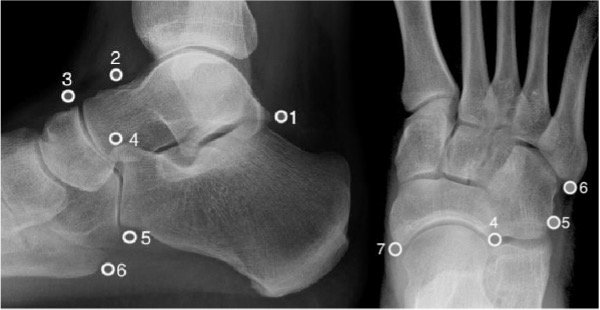

Common accessory ossicles:

- os trigonum

- os supratalare

- os supranaviculare

- os calcaneus secundaris

- os peroneum

- os vesalianum

- os naviculare

Os trigonum

Located posterior to the talus; ~8% of the population.

Os peroneum

Located in the peroneal groove of the cuboid, embedded in the peroneus longus tendon. Associated with peroneus longus tenosynovitis and tear.

Os vesalianum

Located at the fifth metatarsal base. Must be differentiated from an avulsion fracture;

a fracture has a longitudinal orientation and an irregular outline, compared to the transverse orientation and smooth contour of the ossicle.

Os naviculare

Located proximal to the navicular tuberosity (medial side); often embedded in distal tibialis posterior tendon.